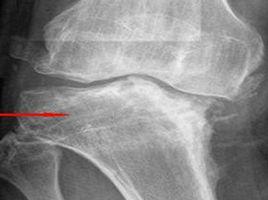

Harrison等[20]給自然緩解下的定義為:在未用藥的情況下患者症狀消失3個月以上。他們研究了358例UA患者其自然緩解率為13%至55%。影響UA自然緩解的因素有:HLA-DR4的出現,缺乏抗CCP抗體,類風濕因子陽性。Emery等[21]對800例早期關節炎患者已觀察3年以上,95%患者接受DMARD治療,病程大於6個月時已有骨質丟失,經治療後骨質丟失也受到抑制。病程最初2年內手骨丟失可高達30%。